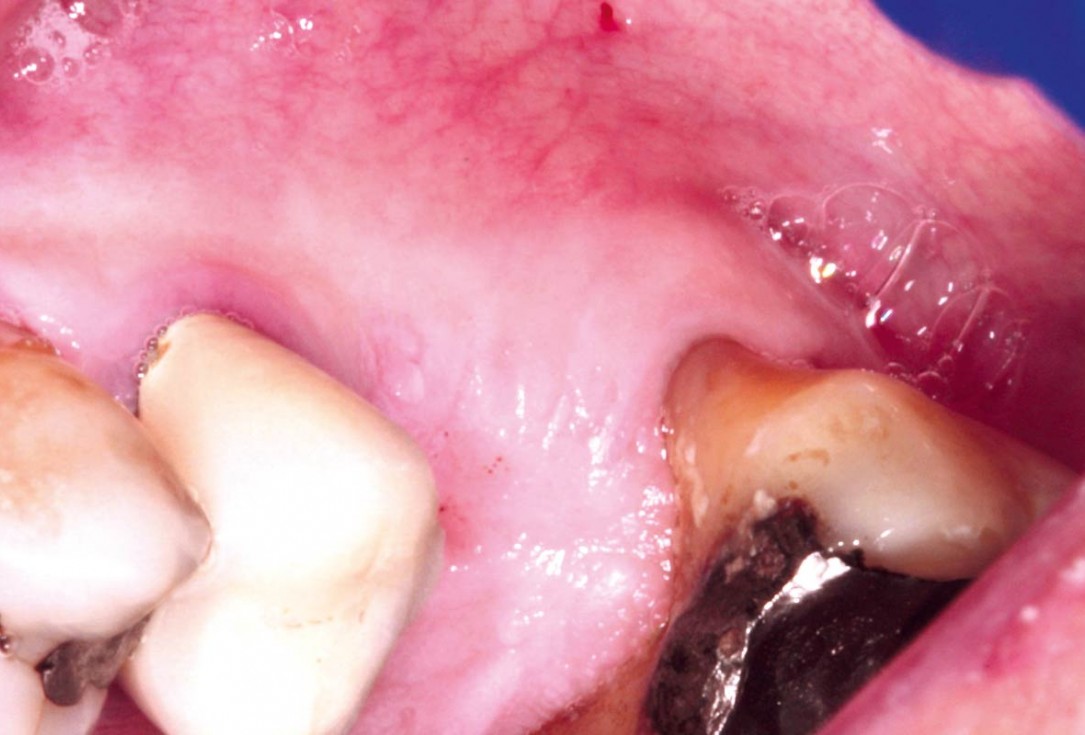

Clinical situation before extraction and implantation